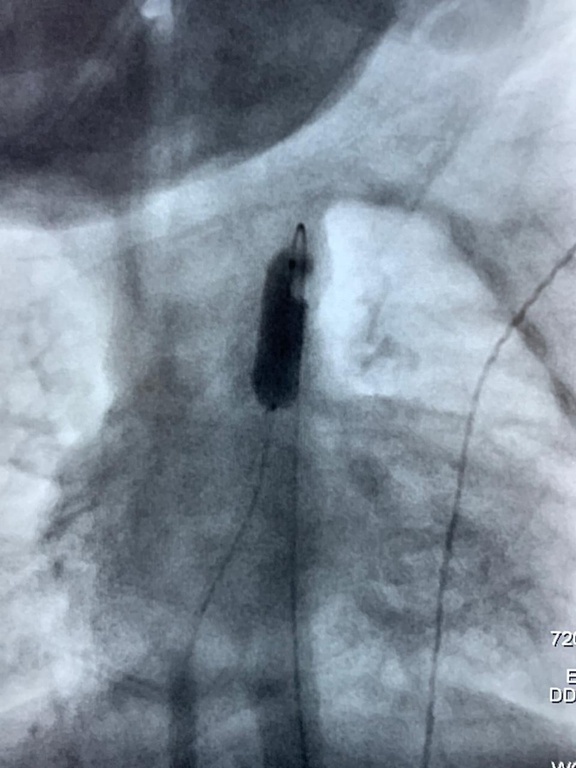

O procedimento foi realizado pela equipe do Serviço de Hemodinâmica do HC-UFU sob o comando do médico cardiologista e responsável técnico, Vilmar José Pereira. Ele explicou que, normalmente, nas cirurgias cardíacas realizadas por vídeo, utiliza-se as veias mais calibrosas (das pernas, por exemplo) para levar os cateteres até o coração. Como Josafá nasceu prematuro, a equipe utilizou a via umbilical e o acesso ao coraçãozinho foi feito por uma veia no umbigo.

“Foi inserido um cateter da veia umbilical até o coração. Esse cateter tem um balãozinho vazio na ponta. Quando chegou lá na válvula do coração que precisava ser tratada, o balãozinho foi insuflado até aumentar de tamanho e abrir o espaço que precisava para o sangue fluir normalmente”, explicou o cardiologista.